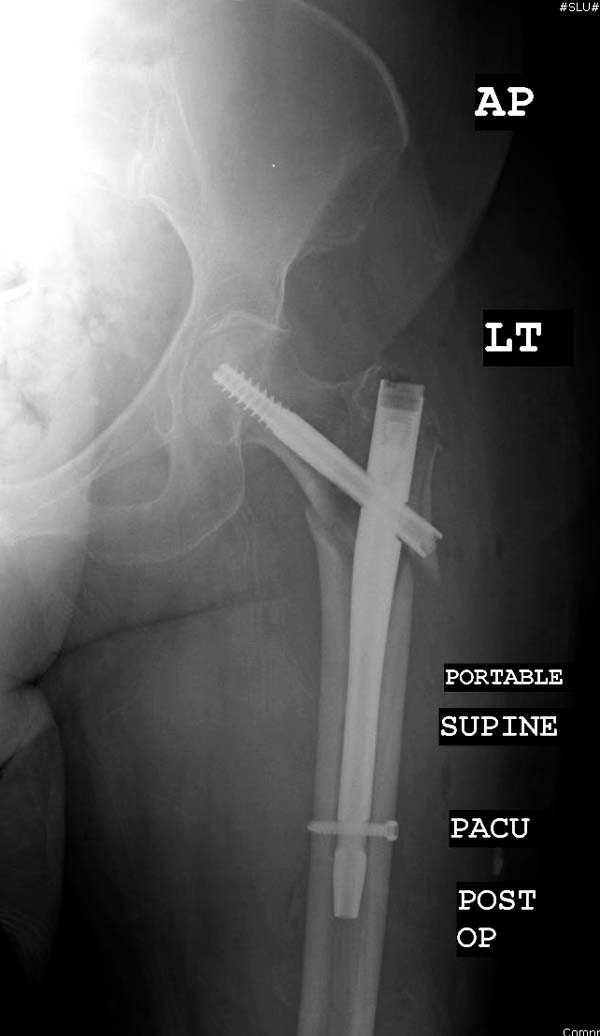

Здесь представлен случай, где в послеоперационном периоде обнаружена техническая ошибка, Gamma 3 установлен с нарушением методики. Больная в 91 лет, прооперирована через день после поступления и выписана через 48 часов.

При первом послеоперационном поликлиническом осмотре больная предъявила жалобы на боли в бедре. В серийных снимках обнаружен продольный перелом верхнего отдела бедра.

Считаем, что техническая ошибка произошла во время установки гвоздя, когда рассверливанию канала не уделили должного внимания. Канал остался узковат, и гвоздь был забит с силой. Полная нагрузка конечности приостановлена на две недели, и боли в конечности изчезли. Больная начала нагрузку и перелом срастается.-- Djoldas Kuldjanov, M.D.Associate ProfessorDepartment of Orthopedic SurgerySt. Louis University

I have a different interpretation of this case. I suspect you did not tighten the set screw all the way in order to allow sliding of the lag screw and fracture fragment compression, as you would for a standard intertrochanteric hip fracture. This is a reverse obliquity fracture, so the result is migration of the proximal segment. I doubt reaming the canal would have prevented this. Had the set screw been fully tightened, there would be no postoperative fragment motion.

I looked at the films again and saw that you are referring to the nondisplaced shaft fracture, not the proximal fragment position. Sorry.

Мне тоже представляется, что это не единственная проблема. Продольные трещины заживают легко и быстро. Интересно, почему увеличился варус и

появилась медиализация дистального отломка.

Мне думается, что варусное положение проксимального отломка на последующих снимках не более чем проекционный феномен. Раскол же диафиза вдоль, наверняка, связан с чрезмерно насильственным введением штифта. Вообще, при реверсивных, да и обычных вертельных переломах, многие давно отказались от короткой Гаммы в пользу long-версии. Но в любом случае надо быть на 100 уверенным в подготовке канала.